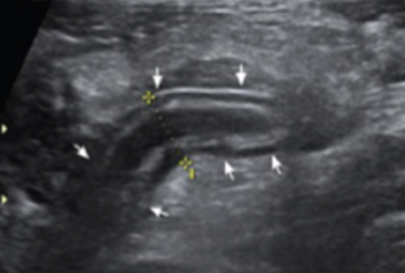

Keyboard sign